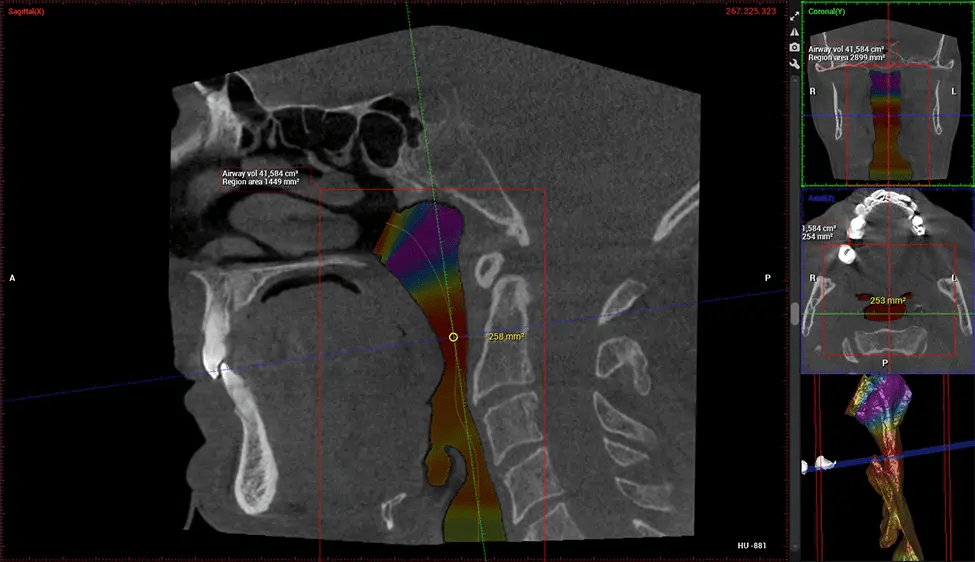

Cone Beam Computed Tomography (CBCT) is an advanced imaging technique used in dentistry and maxillofacial surgery to obtain detailed 3D images of the oral and maxillofacial structures. At Dr G Dental Studio, our CBCT scanners utilize a cone-shaped X-ray beam and a specialized detector to capture images from different angles. A computer then combines these images to create a 3D representation of the patient’s oral anatomy.

This 3D scan, called cone beam computed tomography, gives your dentist a more complete image of your oral anatomy and disease processes than a traditional X-ray. Unlike conventional X-rays, which capture a 2D image of your mouth from various angles, a 3D scan takes multiple digital X-rays for one image. It provides a complete view of your jaw, teeth, nerves, and soft tissues. This enhanced view allows dentists to detect minor issues not visible in traditional 2D scans, such as impacted wisdom teeth or bone fractures in the sinus cavity.

There are many benefits to using CBCT technology, especially compared to the traditional 2D X-ray format. One of the most significant advantages of CBCT scans is that they provide much more information than traditional X-rays. A scan lets your dentist see images from all angles of your jaw and mouth, including your sinuses, nasal cavity, cheekbones, and other surrounding areas. This added information helps your dentist craft a comprehensive treatment plan that addresses all aspects of your oral health.

After the scanning process, the captured X-ray images are processed by the CBCT software, which applies algorithms to reconstruct a detailed 3D image of the scanned area. The software compiles these individual X-ray images and creates a digital 3D representation of the patient’s anatomy. The reconstructed 3D CBCT image can be viewed and analyzed by the dentist or radiologist. This image can be manipulated, rotated, and zoomed in or out to examine specific structures and evaluate the patient’s condition.